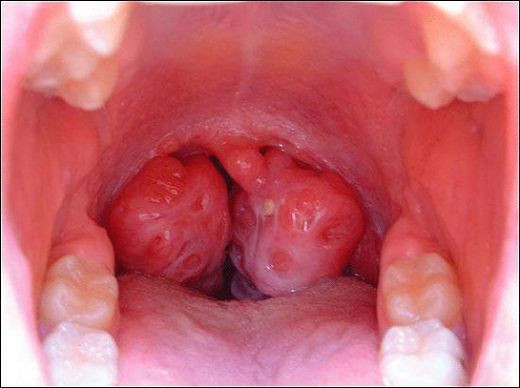

Kronik bademcik iltihabı, genellikle tekrarlayan bademcik enfeksiyonları sonucunda ortaya çıkan ve bademciklerin sürekli iltihaplanmasıyla karakterize edilen bir durumdur. Bu durum, bireylerin yaşam kalitesini olumsuz etkileyebilir. Aşağıda, kronik bademciğin belirtileri, nedenleri ve tedavi yöntemleri detaylı bir şekilde ele alınacaktır. 1. Kronik Bademcik Belirtileri Kronik bademcik iltihabı yaşayan kişilerde gözlemlenen belirtiler şunlardır:

Kronik bademcik iltihabının belirtilerini yaşayan biri olarak, sık sık boğaz ağrısı ve kötü nefes kokusu yaşıyorum. Büyümüş ve deforme olmuş bademciklerim de var. Bu belirtilerle sık sık karşılaşan biri olarak, boğaz enfeksiyonlarımın kronik bademcik iltihabından kaynaklanıyor olabileceğini düşünüyorum. Tedavi için hangi adımları atmam gerek?